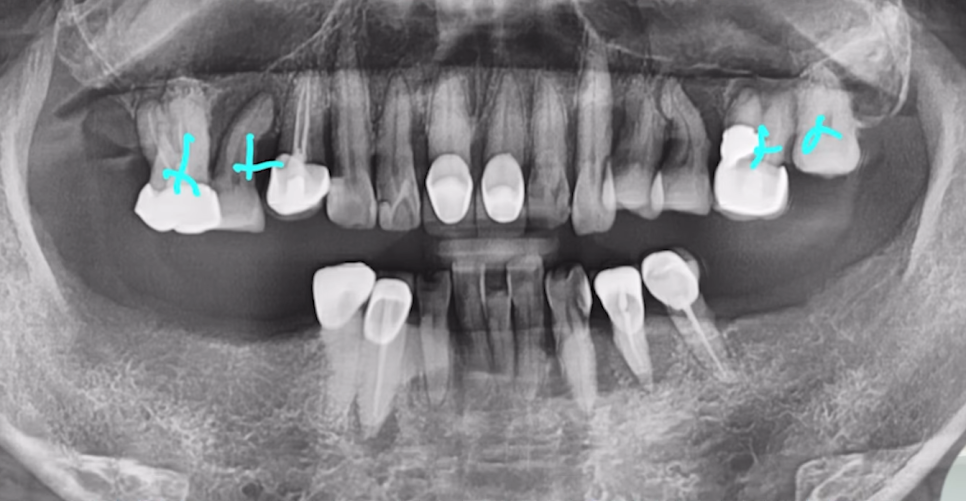

당일에 뼈이식과 상악동 뼈 이식을 해드려 뼈를 충분히 보강한 후, 동시 식립까지 진행했습니다.

상악동에 뼈 잘 이식된 것 보시이죠?

CT 사진으로 잘 식립된 것까지 체크해 드린 후 다음 날 반대편까지 안전하게 심어드렸습니다.

물론 시간은 조금 더 걸렸지만,

잇몸선도 안정적이고 보철물 심미성도 좋게 나왔는데요.